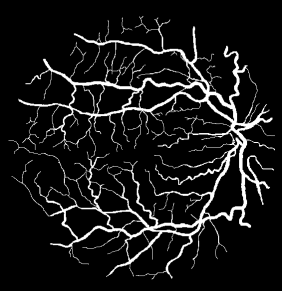

With development of information technology and necessity for high security, using different identification methods has become very important. Each biometric feature has its own advantages and disadvantages and choosing each of them depends on our usage. Retinal scanning is a bio scale method for identification. The retina is composed of vessels and optical disk. The vessels distribution pattern is one the remarkable retinal identification methods. In this paper, a new approach is presented for identification via retinal images using LBP and hog methods. In the proposed method, it will be tried to separate the retinal vessels accurately via machine vision techniques which will have good sustainability in rotation and size change. HOG-based or LBP-based methods or their combination can be used for separation and also HSV color space can be used too. Having extracted the features, the similarity criteria can be used for identification. The implementation of proposed method and its comparison with one of the newly-presented methods in this area shows better performance of the proposed method.